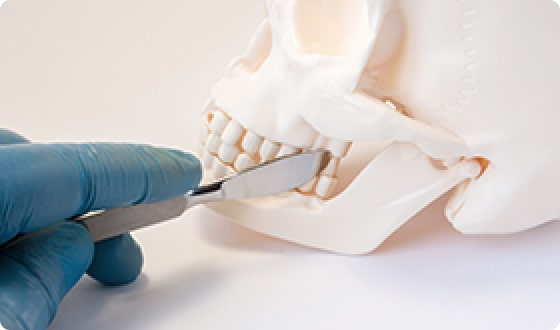

턱관절장애는 턱을 움직일 때 통증, '딱' 소리, 개구 제한 등이

나타나는 기능성 장애입니다. 일상 속에서는 씹기 힘듦, 턱 피로감,

입이 잘 안 벌어지는 느낌으로 불편을 겪게 됩니다.

초음파 유도 시술을 통해

턱관절 장애 통증을 유발하는

심부 근육을 치료할 수 있습니다.

수턱 주변의 심부 근육의 긴장, 턱관절을 형성하는 조직의

염증성 상태가 턱관절 장애를 유발합니다.